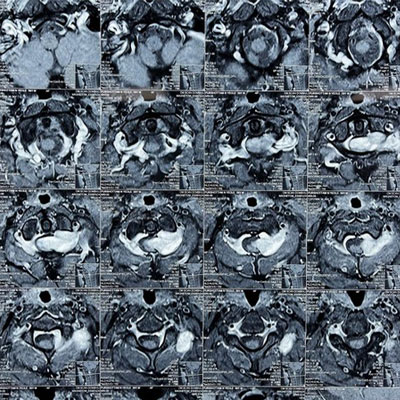

Dr. Ujwal Yeole is an experienced neurosurgeon specializes in treating a wide spectrum of neurological conditions including neuro-oncology, peripheral nerve disorders, vascular disorders, spinal pathologies, pediatric neurosurgery, neuro-trauma and skull base neuroendoscopic procedures.